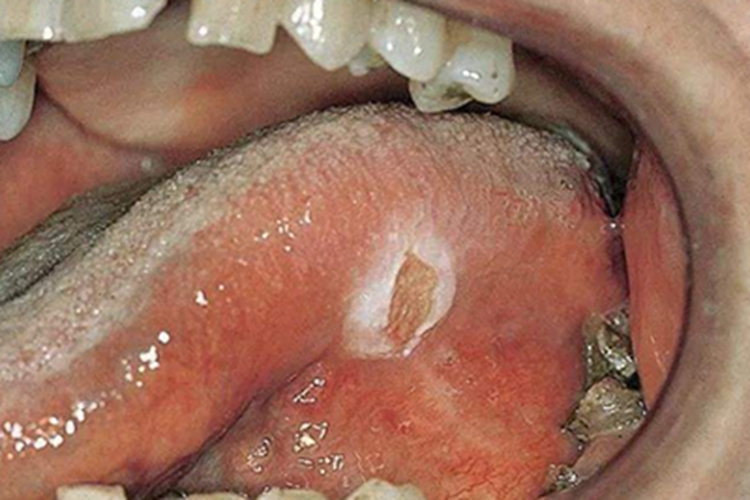

创伤性溃疡可在口腔黏膜出现水疱,之后破损后可形成溃疡或糜烂面,开始时可能仅有轻微疼痛或肿胀,溃疡为形态不整,有角的黏膜缺损,因唾液的浸渍,可使溃疡底发白,周边轻度炎性潮红,自觉疼痛。此外,表面渗出液和唾液混在一起,发生溃疡后可影响进食。

创伤性溃疡主要与口内持久的机械刺激有关,如残冠、残根、不良修复体、锐利的牙齿边缘等。